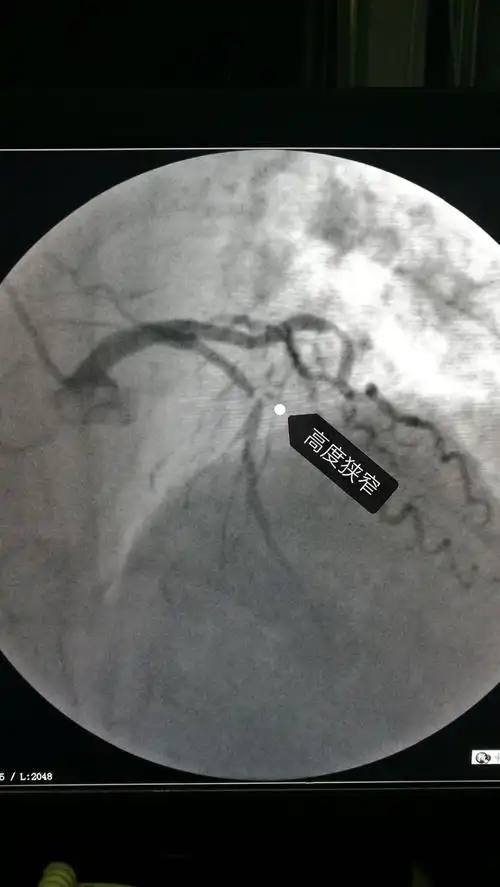

急诊手术,造影发现前降支严重狭窄,血流明显减慢